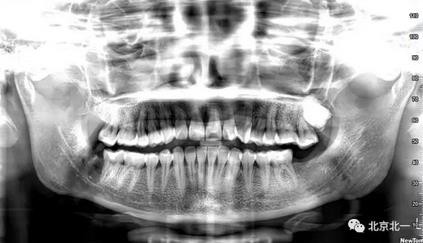

病例資料:一般情況,患者女性,28歲, 主訴:要求拔右側下頜智齒,檢查:右側下頜第三磨牙未見萌出, 拍片如圖。

圖一:CBCT顯示右側下頜水平骨埋伏牙,牙冠距離下牙槽神經(jīng)管接近。

圖二:自帶的CBCT顯示下牙槽神經(jīng)管貼著智齒走形。

圖三:截面圖顯示神經(jīng)管位置。